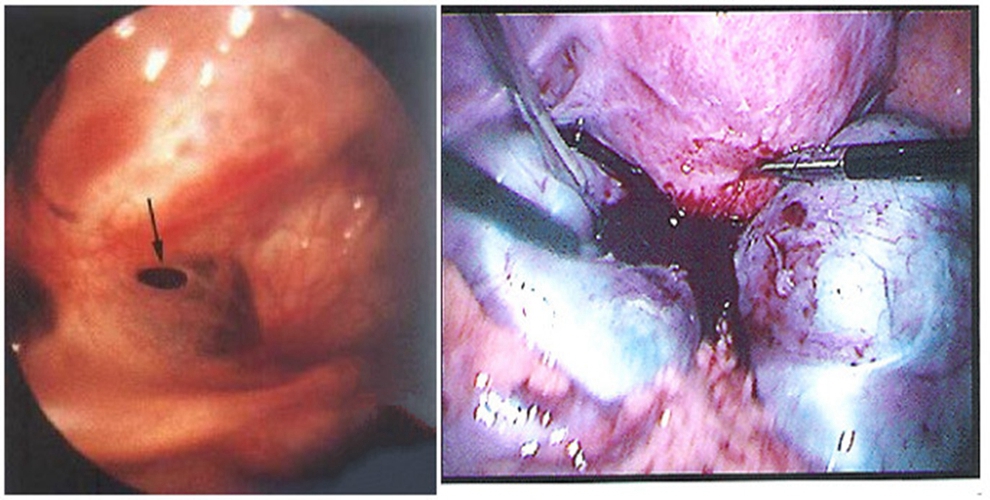

巧克力囊腫圖片

輸卵管囊腫手術